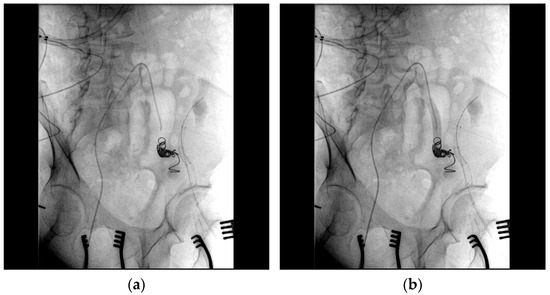

2. Case Report